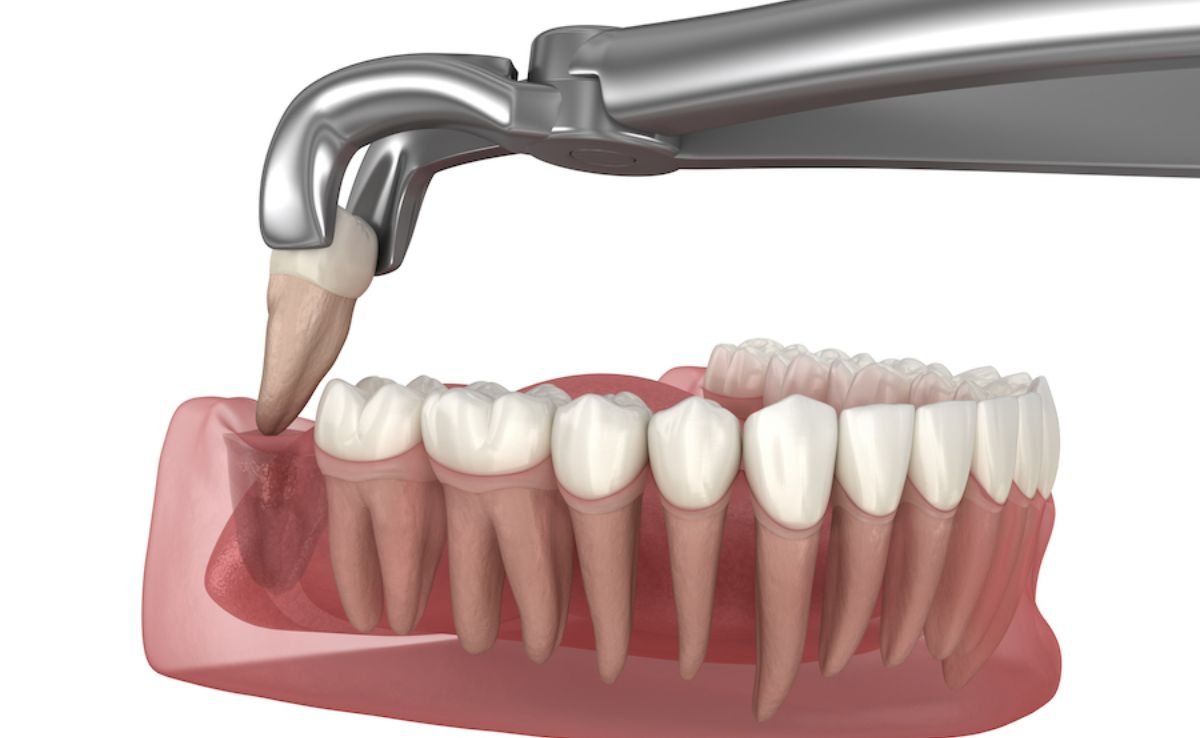

If the tooth has fully erupted above the gum line and is in a straight position, a simple extraction may be performed without the need for surgical intervention.

Impacted or partially erupted teeth require surgical extraction. This involves making an incision in the gum, removing some bone if necessary, and carefully extracting the tooth in one or more pieces.

Once the site is fully anesthetized, the surgeon performs a gingival incision to expose the crown and roots. In cases of deeply impacted wisdom teeth, a small portion of the surrounding bone may be removed using a low-speed surgical handpiece with irrigation. The tooth may be sectioned and removed in segments to reduce trauma to the jawbone and adjacent nerves.